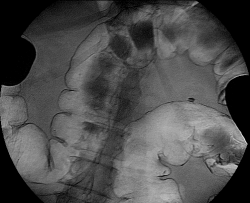

Пациент 76 лет, направлен на ирригоскопию в наше отделение с предворительным обоснованием: образовование восходящего отдела ободочной кишки. Зарание был обговорен хирургом, по поводу выяснения протяженности процесса. Была проведена колоноскопия: "Аппарат проведен до слепой кишки. Просвет толстой кишки нормальный. Стенки толстой кишки эластичные. Толстая кишка нормотоничная. Складки толстой кишки нормальные. Гаустры толстой кишки глубокие. В восходящей кишке виден инфильтрат с бугристой поверхностью, захватывающий все стенки кишки (циркулярно). На поверхности инфильтрата видны мелкие очаги некроза. Инфильтрат суживает просвет кишки. Протяженность инфильтрата до 10 см. ЗАКЛЮЧЕНИЕ: Инфильтративное деонтологическое заболевание_восходящей кишки"

Ваше мнение?

Выложил более информативные сканы. ваше мнение?

Ну "перво - наперво" шикарно видно "сужение"

Это исследование я проводил сегодня утром, помимо данного участка с "органикой" есть ещё один участок, который отчётливо видно на МСКТ при анализе изображений, но почему то мой более старший коллега ни стал об этом указывать ссылаясь на то, что преригатива скопического и эндоскопического исследований, у нас там конечно ни шуточная баталия разгорелась, и вообще поставил данный участой симметричного сужения подвопросом:

Именно этим мне и показался данный случай интересным, получается именно данный участок видели эндоскописты, а это участок поперечного отдела ободочной кишки, даже почти селезёночный угол, чётко видно на МСКТ. И получается что первично-множественный рак толстого кишечника, если я не прав поправте меня.

По-моему, вы правы.

Браво Виталий! А я в очередной раз убедилась: как же прав наш главный хирург настаивая на обязательной ирригоскопии перед операцией...

Описание операции: ЭТН. Срединная лапаротомия. При ревизии в селезеночном углу толстой кишки циркулярная опухоль до 10 см диаметром, в проксимальной трети сигмовидной кишки блюдцеобразная опухоль до 5 см диаметром, заниающая 1/2 окружности кишки, долихосигма. В печени, забрюшинном пространстве, желудке, тонкой кишке патологии не выявлено, желчный пузырь ранее оперативно удален. Мобилизована сигмовидная, нисходящая, поперечноободочная кишка до правой ветви средней толстокишечной аретрии, выполнена левосторонняя гемиколэктомия. Сформирован трансвенрзо-сигмоанастомоз 2-рядным узловым швом. Дефект брыжейки ушит. Гемостаз. Счет салфеток. Трубчатый дренаж в левый боковой канал. Послойные швы на рану.

Описание препарата Удаленная левая половина толстой кишки длиной до 1,2 м с опухолью до 10 см диаметром, циркулярно суживающей просвет и опухолью до 5 см диаметром, блюдцеобразной занимающей 1\2 окружности кишки. В среденй трети сигмовидной кишки дивертикул до 1 см диамером.